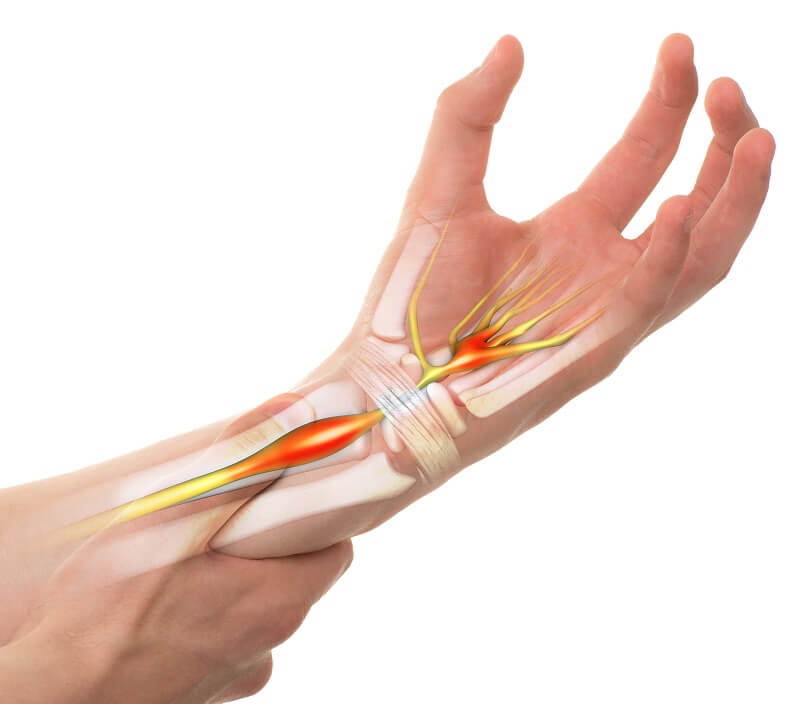

שורש כף יד ואצבעות - אצבע הדק, תסמונת תעלה קרפלית